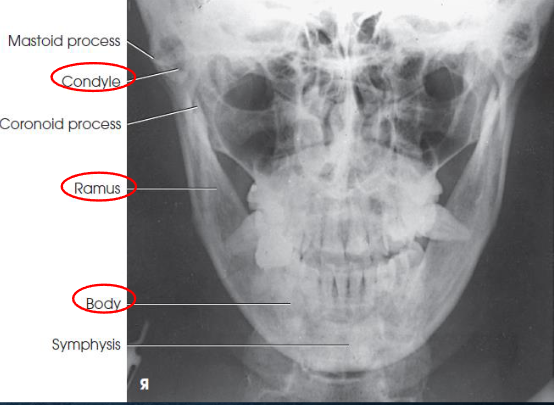

PA axial mandibular rami image criteria

mandibular body and rami

central part of body not well shown due to superimposed spine

demonstrates medial or lateral displace ment of fragments in fractures of the rami

no rotation or tilt:

symmetric mandibular body and rami

MSP of head aligned with long axis of collimated field

condylar processes